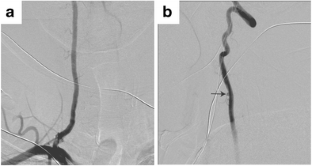

A previously healthy 53-year-old male presented with a 2-month history of pulsatile tinnitus, worsening headaches, and neck pain. Given the clinical symptoms, a workup was initiated to assess for a vascular etiology such as a dural arteriovenous fistula.

Choudhri, O., Dobre, M.C., Feroze, A. et al. Spontaneous regression of an idiopathic arteriovenous fistula of the right vertebral artery. Neuroradiology 60, 221–223 (2018). https://doi.org/10.1007/s00234-017-1963-3